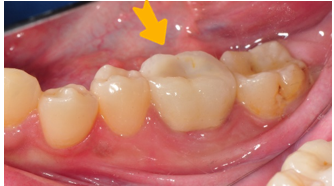

案例:將牙齒從一處拔除, 移植到另外一處

病患因牙根尖發炎,非常疼痛。由於該顆跟尖發炎牙齒從前已做過根管治療,無法再繼續使用,只能拔除。 經醫師評估後,該病患可以做自體牙移植手術,將口內有一顆無作用的智齒移植過來補這個位置。

上排智齒-無作用

1.將上排智齒拔出

2.將智齒植入大臼齒位置,用鐵線固定

等待傷口恢復(約三個月)3.拆除固定鐵線、並將牙齒修型

4.裝上假牙,完成治療